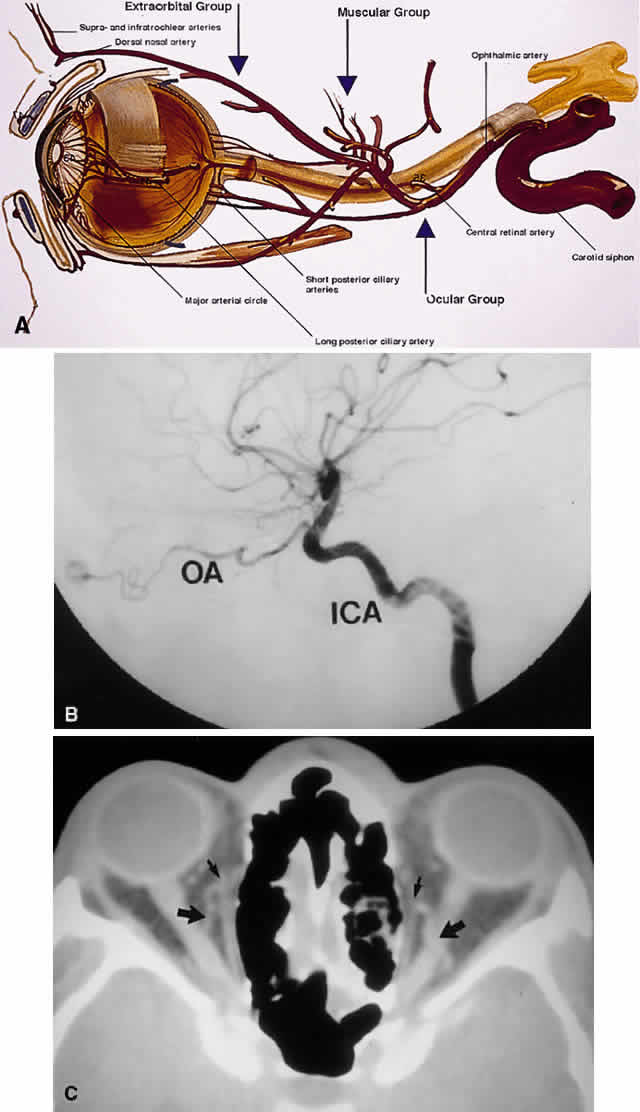

extraorbital (Table 12, Fig. 19). TABLE TWELVE. Three Arterial Groupings (Circles) of the Orbit

Fig. 19. Arterial supply of the orbit. A. The ophthalmic artery enters the orbit to give off its ocular supply, followed

by branches to the extraocular muscles and lacrimal gland, finally

ending superomedially as an extraorbital supply to the eyelids and

glabella. B. Parasagittal arteriography view shows the ophthalmic artery (OA) branching

from the internal carotid artery (ICA) just above the carotid siphon. Note

that although the carotid siphon lies within the CS, the ophthalmic

artery branches off just above the CS. The kink of the ophthalmic

artery within the orbit indicates its course over the optic nerve

from medial to lateral. C. Axial CT image. A fortuitous cut shows the ophthalmic artery looping over

the optic nerve (large arrows). Small arrows indicate the ethmoidal arteries branching off the ophthalmic

arteries to travel through the lamina papyracea. (A modified from Zide BM, Jelks GW: Surgical Anatomy of the Orbit, p 11. New

York, Raven Press, 1985) Fig. 19. Arterial supply of the orbit. A. The ophthalmic artery enters the orbit to give off its ocular supply, followed

by branches to the extraocular muscles and lacrimal gland, finally

ending superomedially as an extraorbital supply to the eyelids and

glabella. B. Parasagittal arteriography view shows the ophthalmic artery (OA) branching

from the internal carotid artery (ICA) just above the carotid siphon. Note

that although the carotid siphon lies within the CS, the ophthalmic

artery branches off just above the CS. The kink of the ophthalmic

artery within the orbit indicates its course over the optic nerve

from medial to lateral. C. Axial CT image. A fortuitous cut shows the ophthalmic artery looping over

the optic nerve (large arrows). Small arrows indicate the ethmoidal arteries branching off the ophthalmic

arteries to travel through the lamina papyracea. (A modified from Zide BM, Jelks GW: Surgical Anatomy of the Orbit, p 11. New

York, Raven Press, 1985)

|